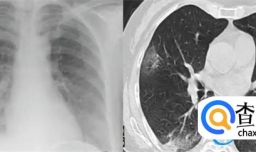

什么情况需要做肺部CT

奥密克戎导致白肺的几率不高吗

曾光回答如何自测肺部是否感染